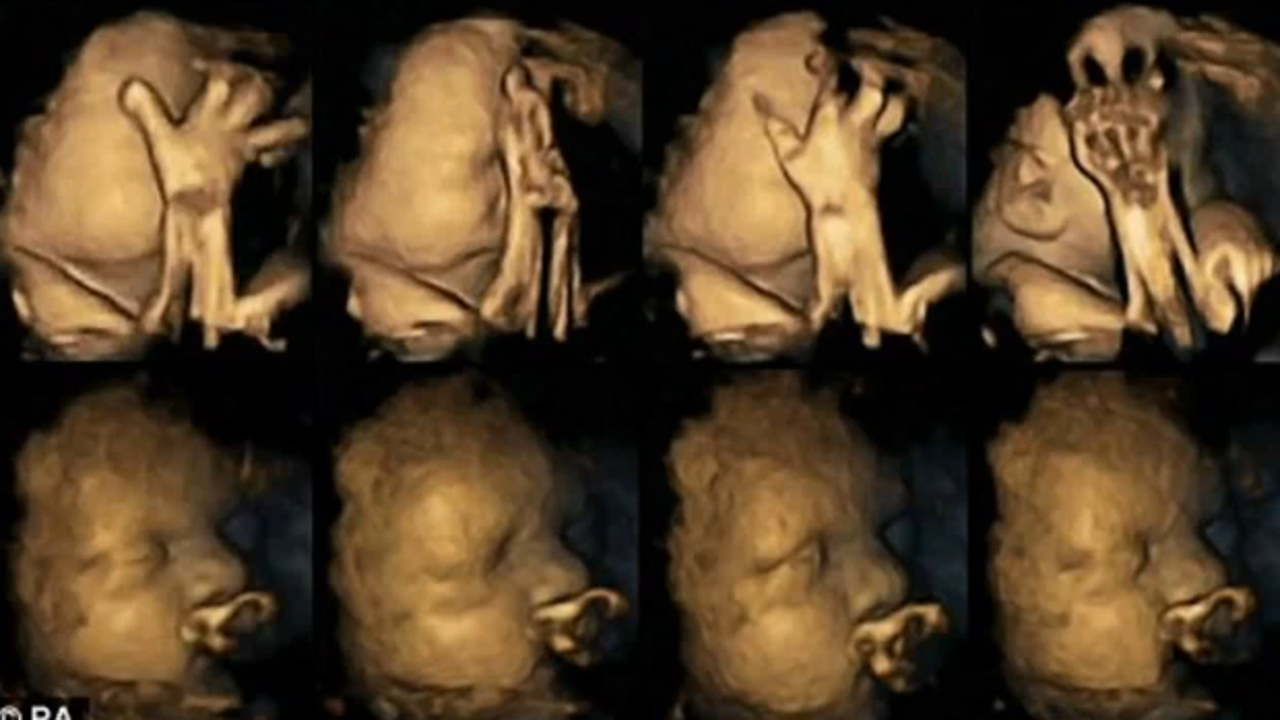

Shocking ultrasound images show what smoking does to unborn babies

A study of ultrasound scans is revealing how the development of unborn babies can be affected when their mothers smoke during pregnancy.

Ultrasound scans of unborn babies whose mothers smoked showed a "significantly higher" rate of mouth movement than the normal declining rate of movements expected in a healthy fetus.

"Fetal facial movement patterns differ significantly between fetuses of mothers who smoked compared to those of mothers who didn’t smoke," said Dr. Reissland.

“Technology means we can now see what was previously hidden, revealing how smoking affects the development of the fetus in ways we did not realize," said co-author Brian Francis, of Lancaster University. "This is yet further evidence of the negative effects of smoking in pregnancy.”